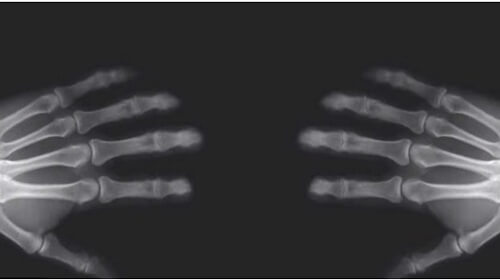

A joint is a location where two bones meet. All joints are made up of an area known as a joint capsule. The joint capsule protects the joint and contains a natural lubricant known as synovial fluid. This fluid is necessary for healthy joint movement.

It’s precisely this lubricant that’s responsible for the infamous “cracking” sound. That’s because there is dissolved air inside the joint capsule that you release when you apply force to your knuckles. Small air pockets escape quickly, and the characteristic sound occurs.

After you crack your knuckles it’s not possible to repeat it immediately, because the joint has to settle back to its normal position and more air must dissolve into the synovial fluid. But after about fifteen minutes, it’s possible to crack the same knuckles again.